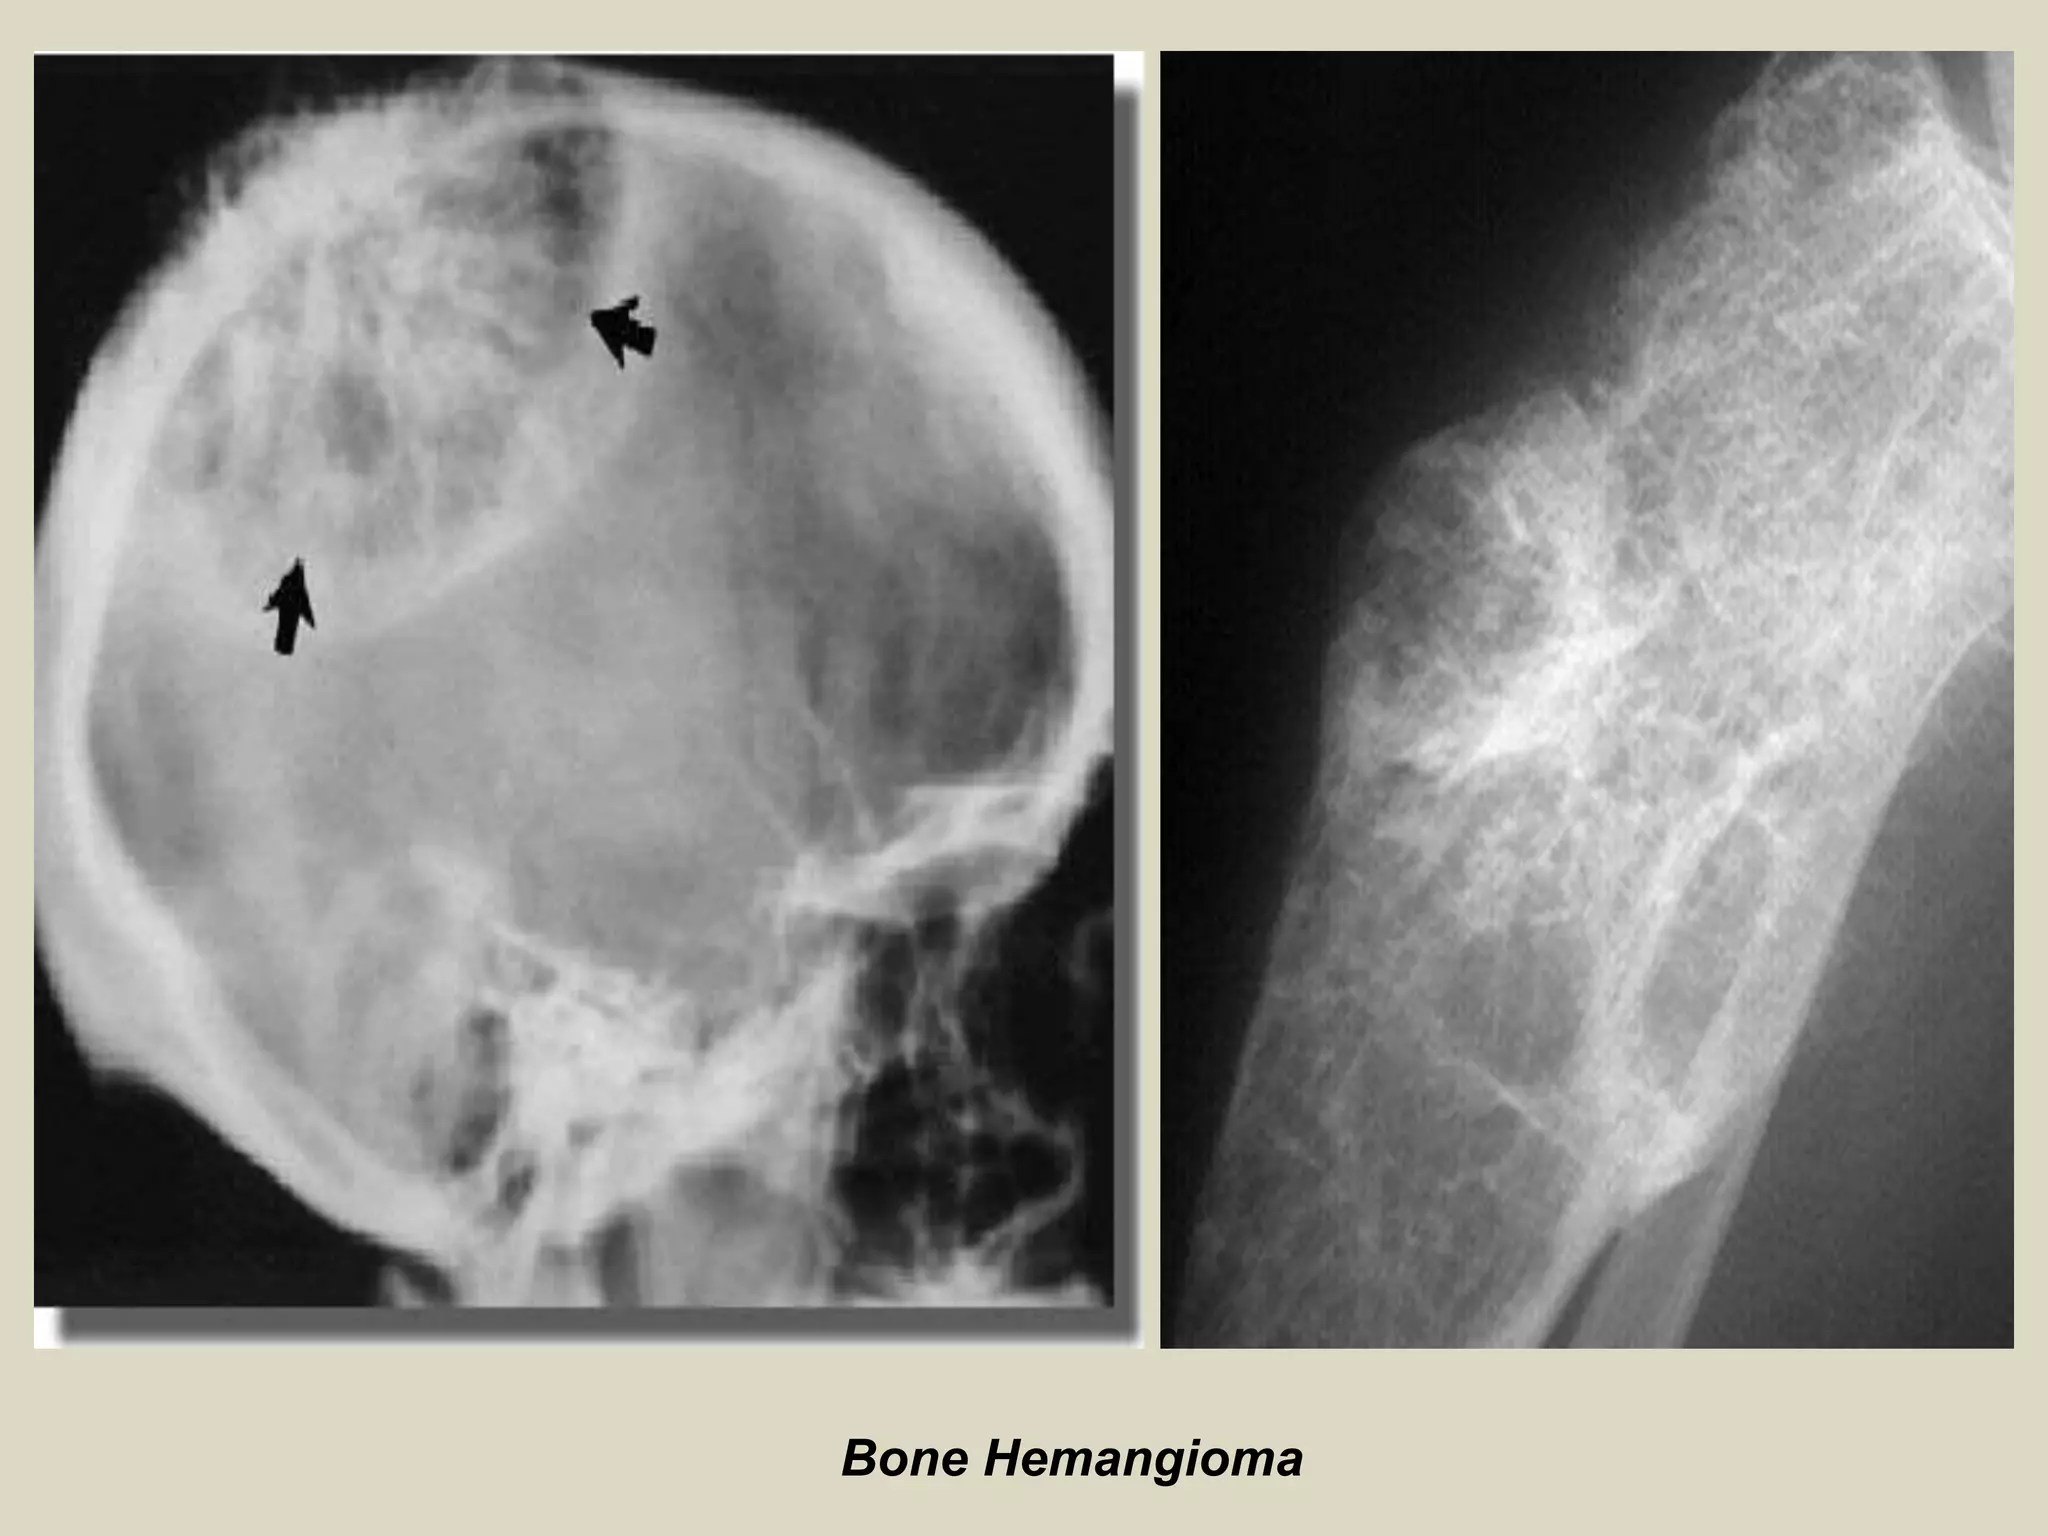

HEMANGIOMA OF BONE

Definition:

- Hemangioma is benign solitary tumor composed of newly

formed vessels of capillary or cavernous type.

Epidemiology:

- Wide age distribution, ranging from the first to eight decades

of life, with nearly 70% of the cases diagnosed in patients

between 30 and 60 years.

- Occasionally hemangiomas become clinically evident during

the first decade of life. There is no sex predilection.

- They are rare in newborns and infants and reported cases

have arisen in the skull bones.

- The tumors are usually solitary, but multifocal neoplasms

have been described most frequently in the vertebral

columns.

Sites of involvement:

- Hemangiomas frequently occur in craniofacial bones ,

predominantly in calvarium (50%), followed by the

spine (20%).

Clinical findings:

- Relatively common asymptomatic.

Imaging:

- Hemangiomas present as lucent, well demarcated defects.

- In flat bones, they markedly expand the bone contour and

produce rarefaction with radially oriented striations.

- Vascular nature of the lesion often is suggested by its bubbly

or honeycomb trabeculated appearance.

- Overlying cortex is expanded and thinned, but complete cortical

disruption and invasion into soft tissue are not present.

- Characteristic sunburst appearance of hemangioma is seen

in skull lesion (not confuse with that seen in osteosarcoma

of long bones).

- Smaller lesions may present as Intracortical rarefaction with

or without a honeycombed appearance and adjacent

sclerosis.

- MRI of hemangiomas generally reveals a low signal on T1-

weighted images and a high signal on T2 weighted images

(fluid content of tumor vessels).

Bone Hemangioma